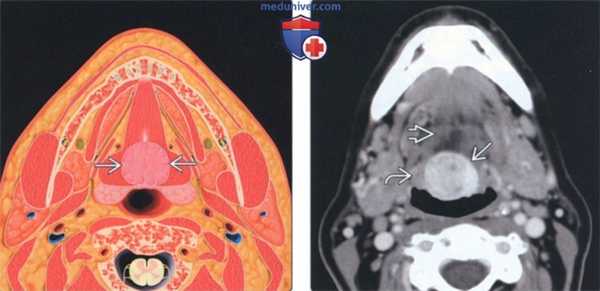

(Слева) КТ с КУ, аксиальная проекция. Подслизистое образование с четкими контурами, расположенное вдоль средней линии дна полости рта. Неоднородная плотность говорит о возникновении зоба.

(Справа) При МРТ Т1ВИ в сагиттальной проекции определяется неоднородное гиперинтенсивное образование, расположенное вдоль средней линии корня языка. Обратите внимание на сужение просвета ротоглотки, а также смещение надгортанника кзади и книзу.

(Слева) На аксиальной КТ с КУ в области дна по средней линии определяется объемное образование с четкими контурами, представленное эктопической тканью щитовидной железы неоднородной плотности (может быть сопоставимо с ранними изменениями при зобе).

(Справа) На сагиттальной MPT (STIR, срединный срез) в основании языка визуализируется объемное образование с неоднородным гиперинтенсивным сигналом, заполняющее валлекулу. В этом случае язычная щитовидная железа обусловливает значительное сужение просвета ротоглотки, смещая надгортанник кзади и книзу.